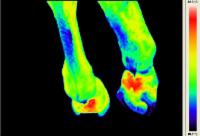

Walzertraum - Pferd nach Sehnen-OP - Horse after tendon operation